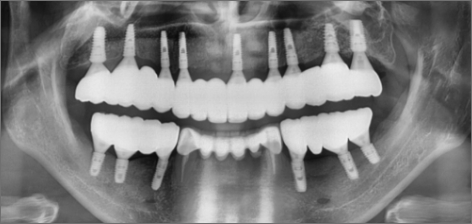

10년 후 : 2024.02.03

치료 기간 : 2014.01.18 ~ 2024.02.03

THE 이해승치과에서 2014년 치료 받으신 40대 환자분의 사례입니다. 흡연과 음주가 근본 원인이 되어 2014년 전악 임플란트 치료를 받으셨습니다. 감사하게도 저희와 함께 꾸준히 10년 관리를 동행해오시면서 추가적인 전신 질환 없이 건강한 50대를 보내고 계십니다. 치료 경험을 통해 변화를 만드신 환자분을 존경합니다.